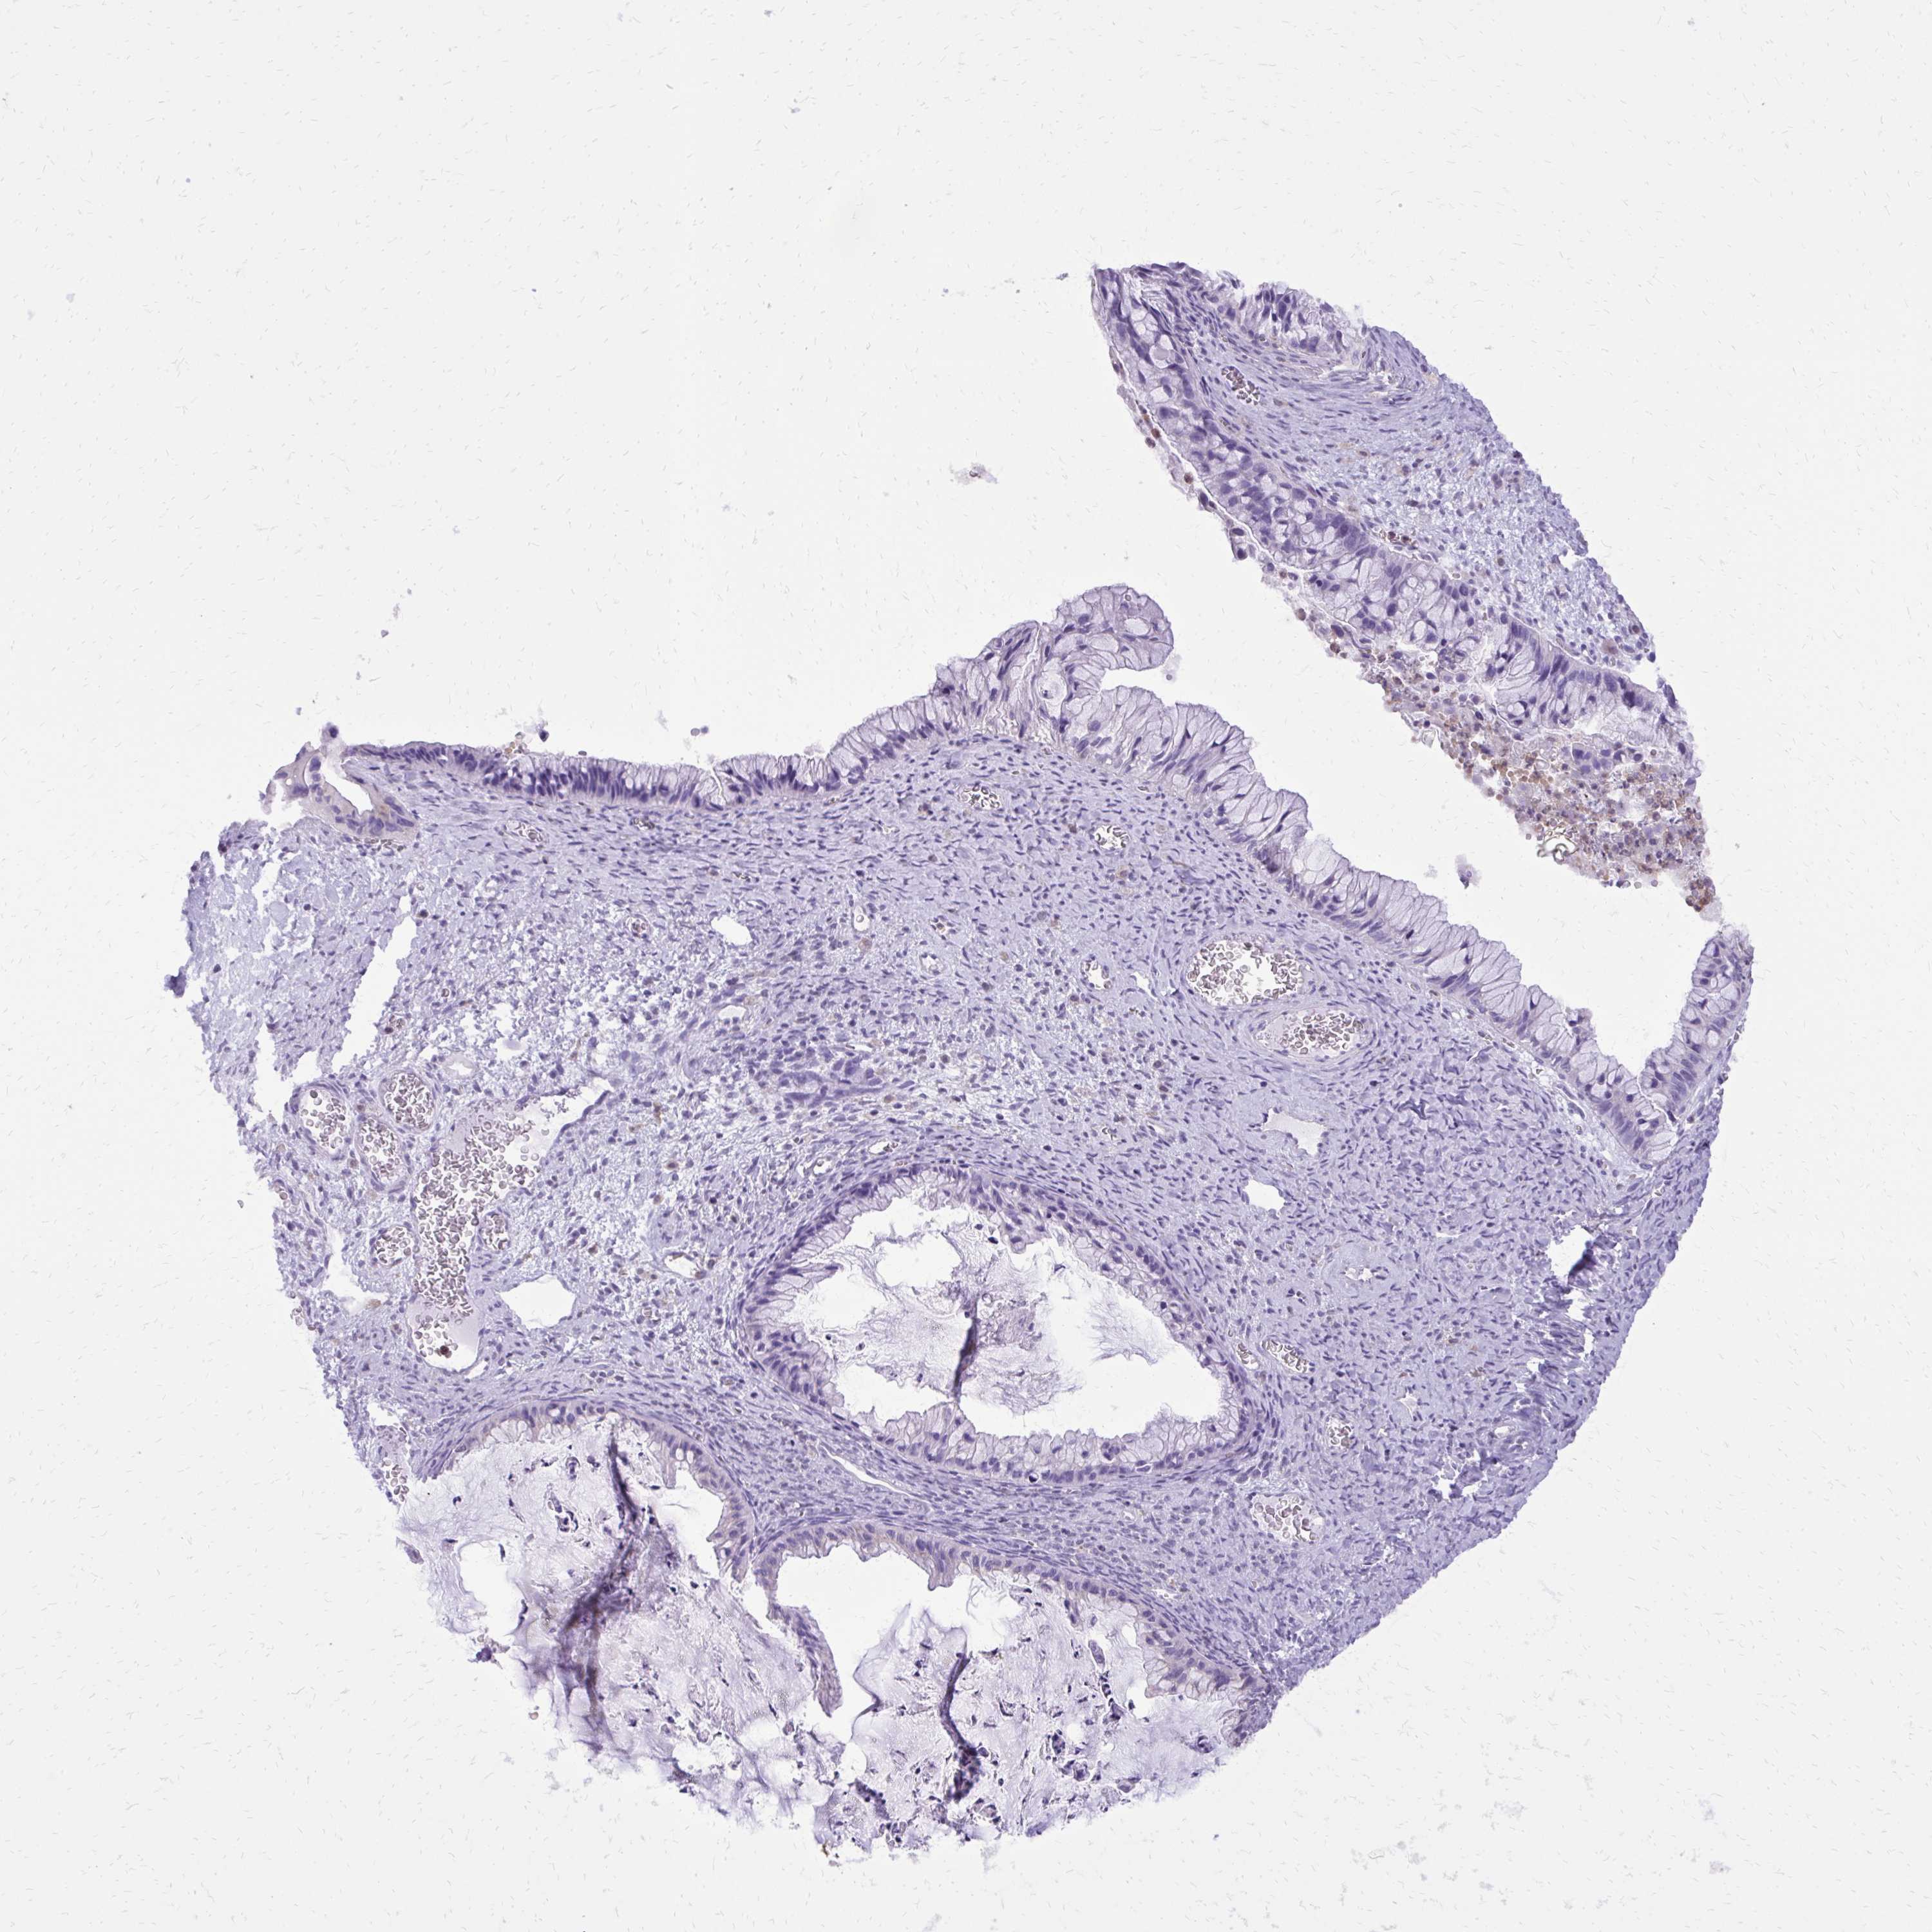

OVARIAN CANCER - Protein expressioni

A mouse-over function shows sample information and annotation data. Click on an image to view it in a full screen mode. Samples can be filtered based on level of antibody staining by selecting one or several of the following categories: high, medium, low and not detected. The assay and annotation is described here.

Note that samples used for immunohistochemistry by the Human Protein Atlas do not correspond to samples in the TCGA dataset.

Antibody stainingi

Antibody staining in the annotated cell types in the current human tissue is reported as not detected, low, medium, or high, based on conventional immunohistochemistry profiling in selected tissues. This score is based on the combination of the staining intensity and fraction of stained cells.

Each image is clickable and will lead to virtual microscopy that enables deeper exploration of all samples and also displays staining intensity scores, fraction scores and subcellular localization as well as patient and tissue information for each sample.

Antibody HPA051282

Antibody HPA055838

Antibody CAB001515

Cystadenocarcinoma, serous, NOS

Cystadenocarcinoma, mucinous, NOS

Carcinoma, endometroid